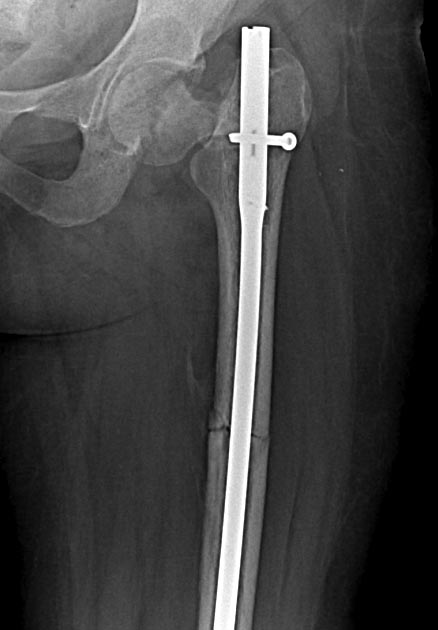

Две несросшихся шейки бедра, пацинтка 27 лет, травме 5 месяцев

Травма 5 месяцев назад кататрвма.

БИОС плеча, Чкдо на л/запястный сустав, Биос левого бедра, Мос правой шейки

бедра винтами.

Причина обращения -выявленный ложный сустав шейки левого бедра. При

дообследовании выявлен несросшийся перелом шейки бедра на винтах.

Опороспособность обеих н/конечностей резко снижена, может стоять на правой,

передвигается на каляске.Что думаем: слева однозначно протез, но бедро не

срослось, менять гвоздь на пластину, пластина или которкая, или опасность

конфликта с ножкой протеза, можно подождать консолидации и разбираться с

правой конечностью.Справа остесинтез с коррегирующей остеотомией, но смущает

состояние верхнего полюса после миграции винтов, что может повлечь

протезирование на фоне нарушения анатомии проксимального бедра, что не

хорошо для выживаемости протеза у 27 летней пациентки. Может сразу протез

?КТ головки не информативна из-за винтов